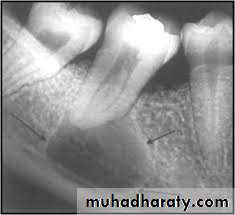

Cysts (abnormal, closed-walled sac present in or around tissue): usually X-ray detected and removed before they enlarge and destroy bone tissue. Some types are:A- Dentigerous: cystic sac containing a tooth or tooth bud particle.

B- Radicular: cyst located alongside or at the apex of a Tooth root; also called periapical cyst.C- Ranula: cystic tumor found on the underside of the tongue or in the sublingual or submaxillary ducts; usually the result of a blocked duct.